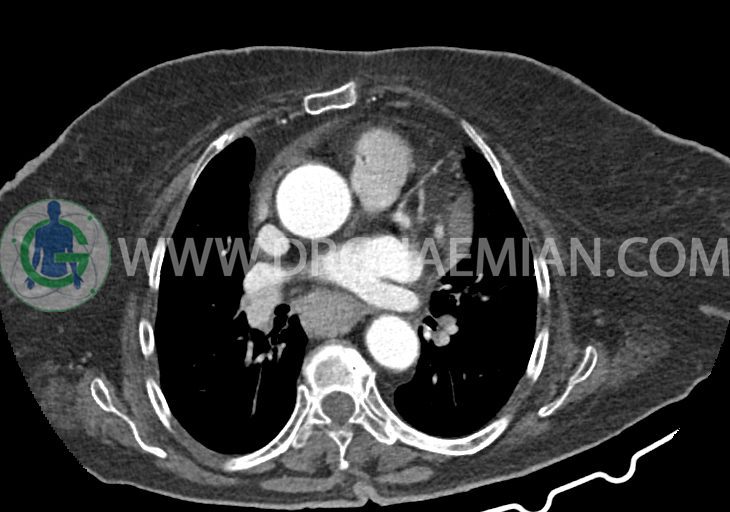

در سی تی اسکن اسپیرال ریه و مدیاستن – شکم و لگن با و بدون کنتراست خوراکی و وریدی (مولتی دیدکتور 16 با مقاطع ظریف و بازسازی های ساژیتال و کرونال):

–کاردیومگالی همراه با pericardial effusion خفیف

–یک ندول به ابعاد 19x18mm با حدود اسپیلوکه در سگمان لترال RML و دو ندول کوچکتر در مجاورت فوقانی آن به اقطار 6mm و 5mm ( مطرح کننده کارسینوم برونکوژنیک یا متاستاز )

–دیلاتاسیون نیمه فوقانی مری توراسیک ناشی از افزایش ضخامت circumferential توده مانند در یک سوم دیستال مری به طول 50mm ، که می تواند مطرح کننده انفیلتراسیون تومورال همراه با تنگی

–لنف نودهای non significant مدیاستینال با حداکثر SAD=6mm در فضای پره کارینا

–آئورت صعودی دیلاته به قطر 38mm